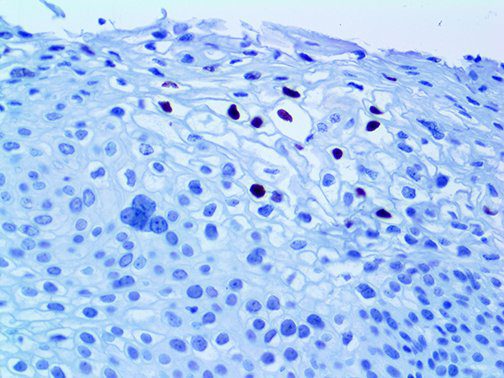

It is the ICU physician who is most likely to witness one of the deadliest manifestations of the abnormal immunological response, the cytokine storm syndrome (CSS). This response is also referred to by some as the cytokine release syndrome (CRS). CSS is characterized by continuous activation and expansion of macrophage and lymphocyte populations, which secrete large amounts of cytokines, causing the cytokine storm. This massive cytokine release is akin to hemophagocytic lymphohistiocytosis (HLH) disease, a syndrome characterized by initial unchecked and persistent activation of cytotoxic T lymphocytes and NK cells.